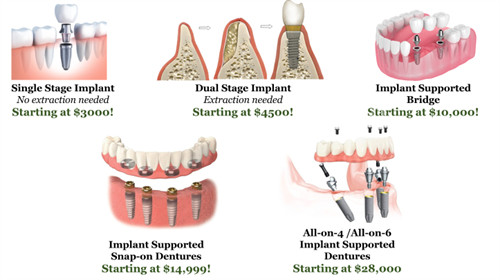

若总价远低于市场均价(如单颗低于3000元),需谨慎核实材料品牌及医生资质。